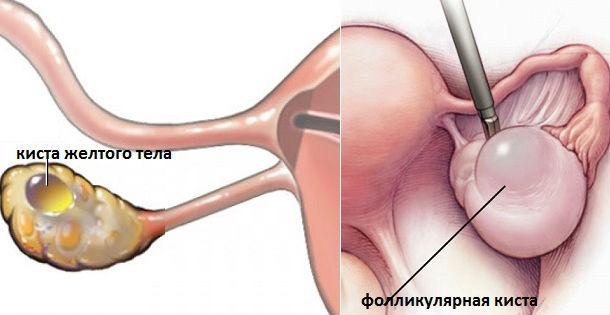

Гистологические изображения фолликулярной кисты яичника